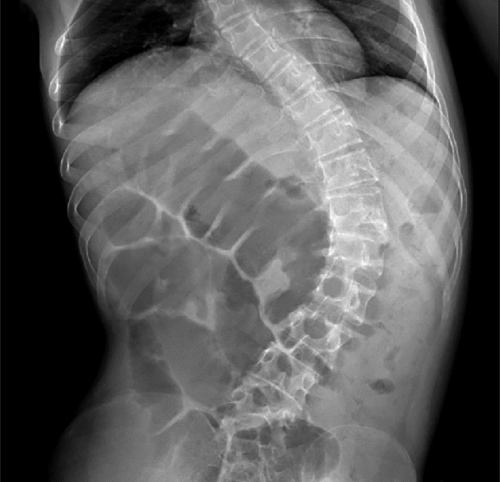

المريضة (أ): فتاة عمرها 16 عامًا مصابة بانحناء شديد (60 درجة)، تعاني من إمساك متكرر وتأخر في حركة الأمعاء.